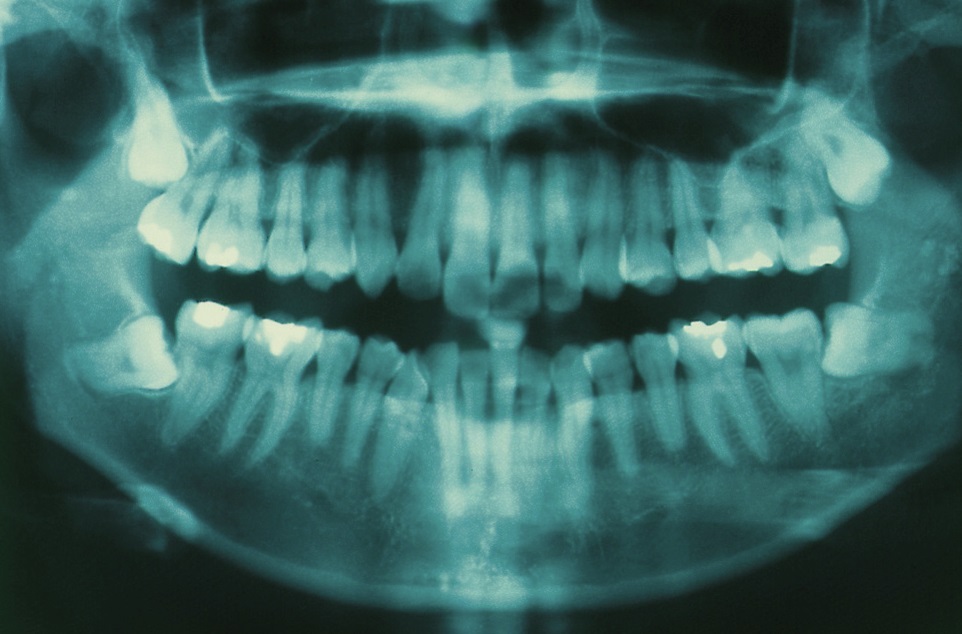

Примеры ортопантомограмм и их анатомия

Раздел: Фотоэссе